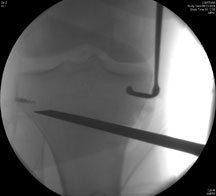

This picture on the left shows the fixation with an anchor on the side to put his ligaments back on again. As part of the osteotomy you can see the drill in position on the inner side of the leg, and that is aiming almost at the fibula. The next image on the right shows the chisel going in under X-ray guidance – the wire is the drill bit and then the slightly flat looking thing is the chisel.